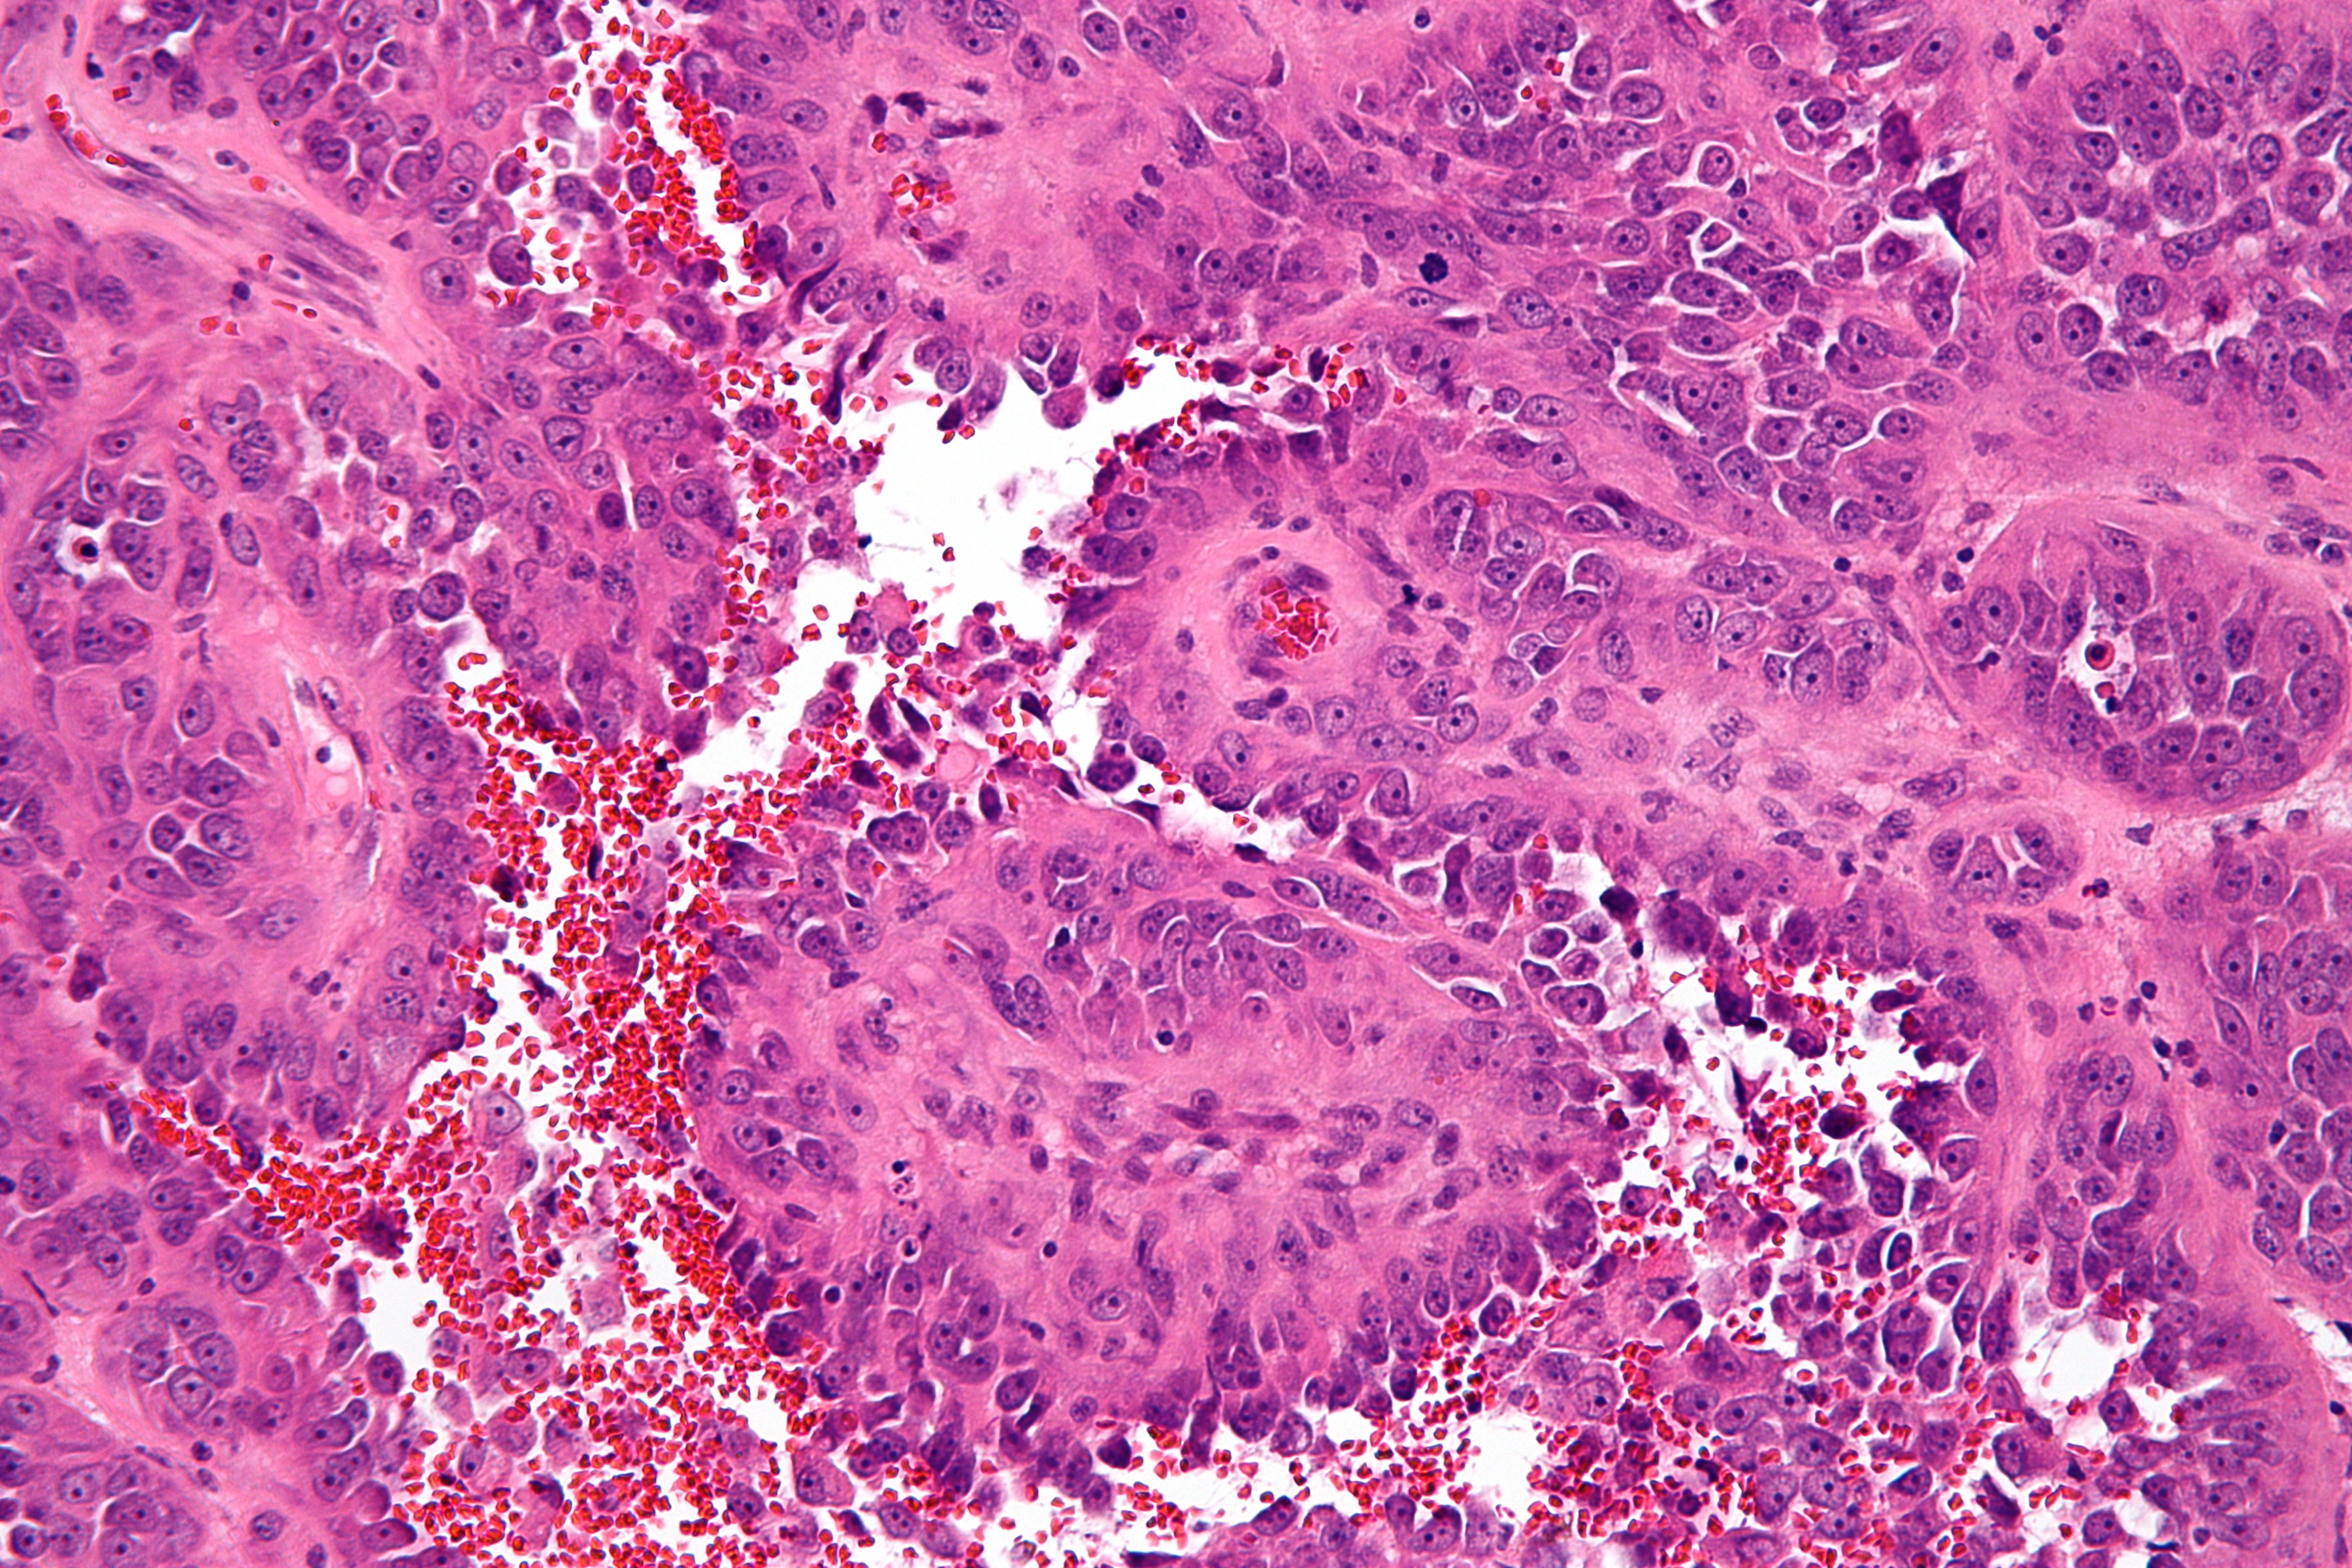

![Histologie angiosarcoma (click on photo to enlarge) [source: Nephron - Wikimedia - Creative Common License 3.0] Histologie angiosarcoma](../../../images/angiosarcoma-2z.jpg) |

![Histologie epithelioid angiosarcoma (click on photo to enlarge) [source: Kevin Kwee / Afdeling Pathologie MUMC] Histologie epithelioid angiosarcoma](../../../pacoupes/thumbnails/epitheloid-angiosarcoom.jpg) |

![Histologie epithelioid angiosarcoma (click on photo to enlarge) [source: Kevin Kwee / Afdeling Pathologie MUMC] Histologie epithelioid angiosarcoma](../../../pacoupes/thumbnails/angiosarcoom.jpg) |

| angiosarcoma |

ingescande coupe (zoom) |

Foto rechtsboven:

www.webpathology.com.

Foto linksonder: Michael Bonert (Nephron) - Wikimedia (Creative Common License

3.0).

Foto's midden en rechts onder,

hoge resolutie PA-foto's: Kevin Kwee en Afdeling Pathologie MUMC. Klik

op de afbeelding om in te zoomen.

PA:

Vasculaire proliferatie met veel mitosefiguren. De cellen zijn positief voor

markers voor vaten (CD31, CD34, FVIII-related antigen) en lymfvaten (D2-40).